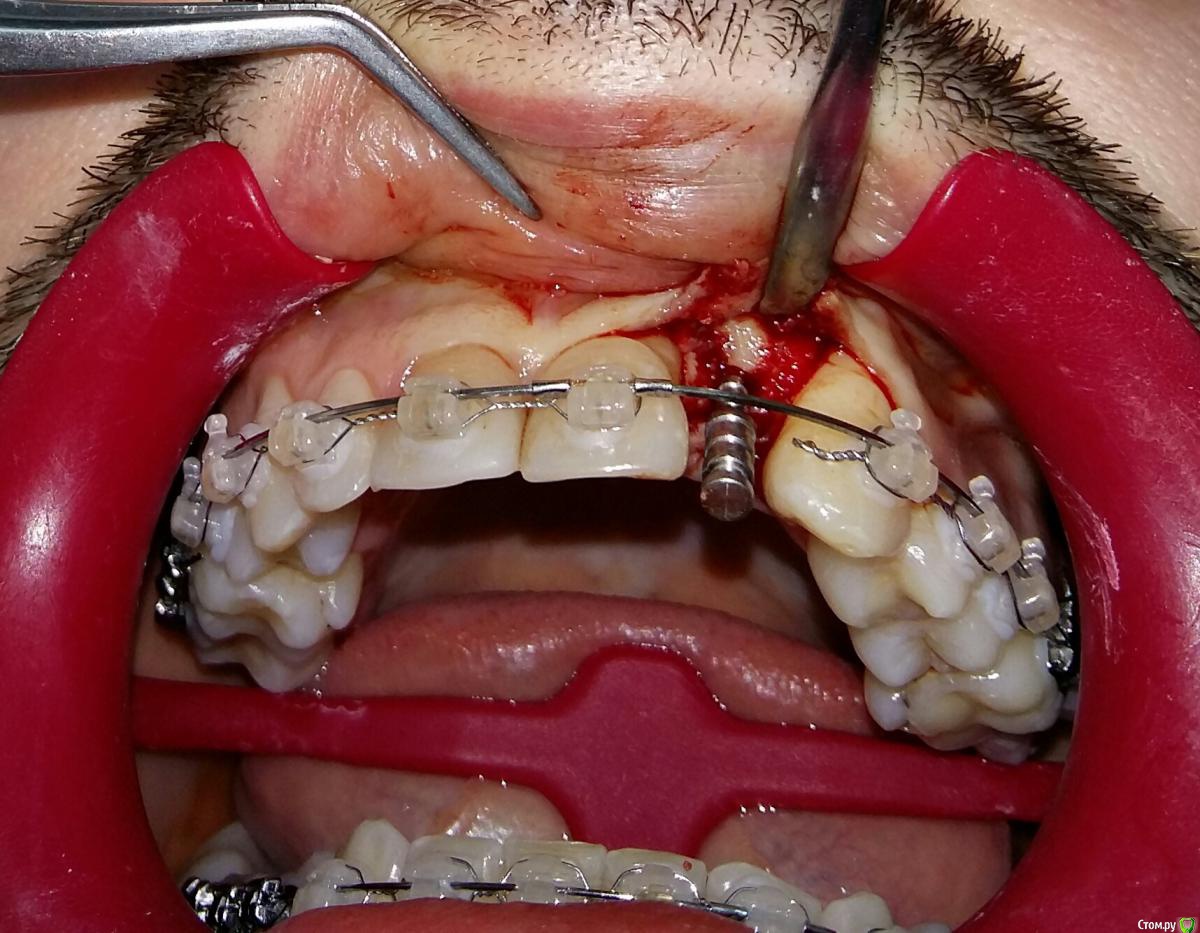

Kostoprav Опубликовано 8 июля, 2015 Поделиться Опубликовано 8 июля, 2015 ИЗНАЧАЛЬНАЯ СИТУАЦИЯ ПОЛУЧИЛОСЬ сори что нет фото до имплантации. Блок взял с тела челюсти, фиксировал двумя винтами (во время имплантации выкрутил только один), присыпал gen os, укрыл дермой-получил заметный прирост слизистой) имплант альфадент 3,75х11,5 2 Ссылка на комментарий

Kostoprav Опубликовано 8 июля, 2015 Автор Поделиться Опубликовано 8 июля, 2015 Видно что блок прирос. ЗдоровоОстальное оценить сложноМне нравится положение импланта в плане оси.Но уровень заглубления не ясенТакже не видно прироста десныВ общем мало данных для оценкиНо опять же вам именно она и нужна?по вестибюлярной поверхности заглубил приблизительно на 1мм с небной больше получилось. слизистая по сравнению с первым разом значительно толще стала, доказать к сожалению не могу так как не делал фото(: я выложил этот пост не только ради оценки, может кому из начинающих данный случай сгодиться 3 Ссылка на комментарий

Kostoprav Опубликовано 8 июля, 2015 Автор Поделиться Опубликовано 8 июля, 2015 На что ориентировались, позиционируя платформу по вертикали?ориентацию задавал ортопед, стоял рядом за спиной и командовал Ссылка на комментарий

k.t.m. Опубликовано 8 июля, 2015 Поделиться Опубликовано 8 июля, 2015 Дуга вестибулярная -отличный позиционер вестибуло-)))) 3 Ссылка на комментарий